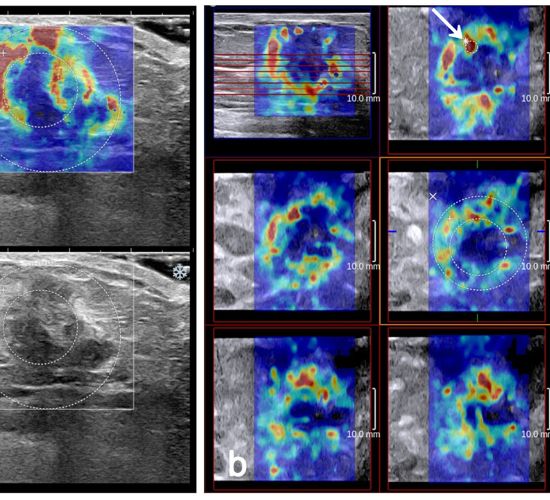

الاستوگرافی پستان: از این روش برای اندازه‌گیری سختی بافت‌های پستان استفاده می‌شود تا تغییرات بافتی مشکوک به تومور یا سرطان شناسایی شود.

الاستوگرافی پستان